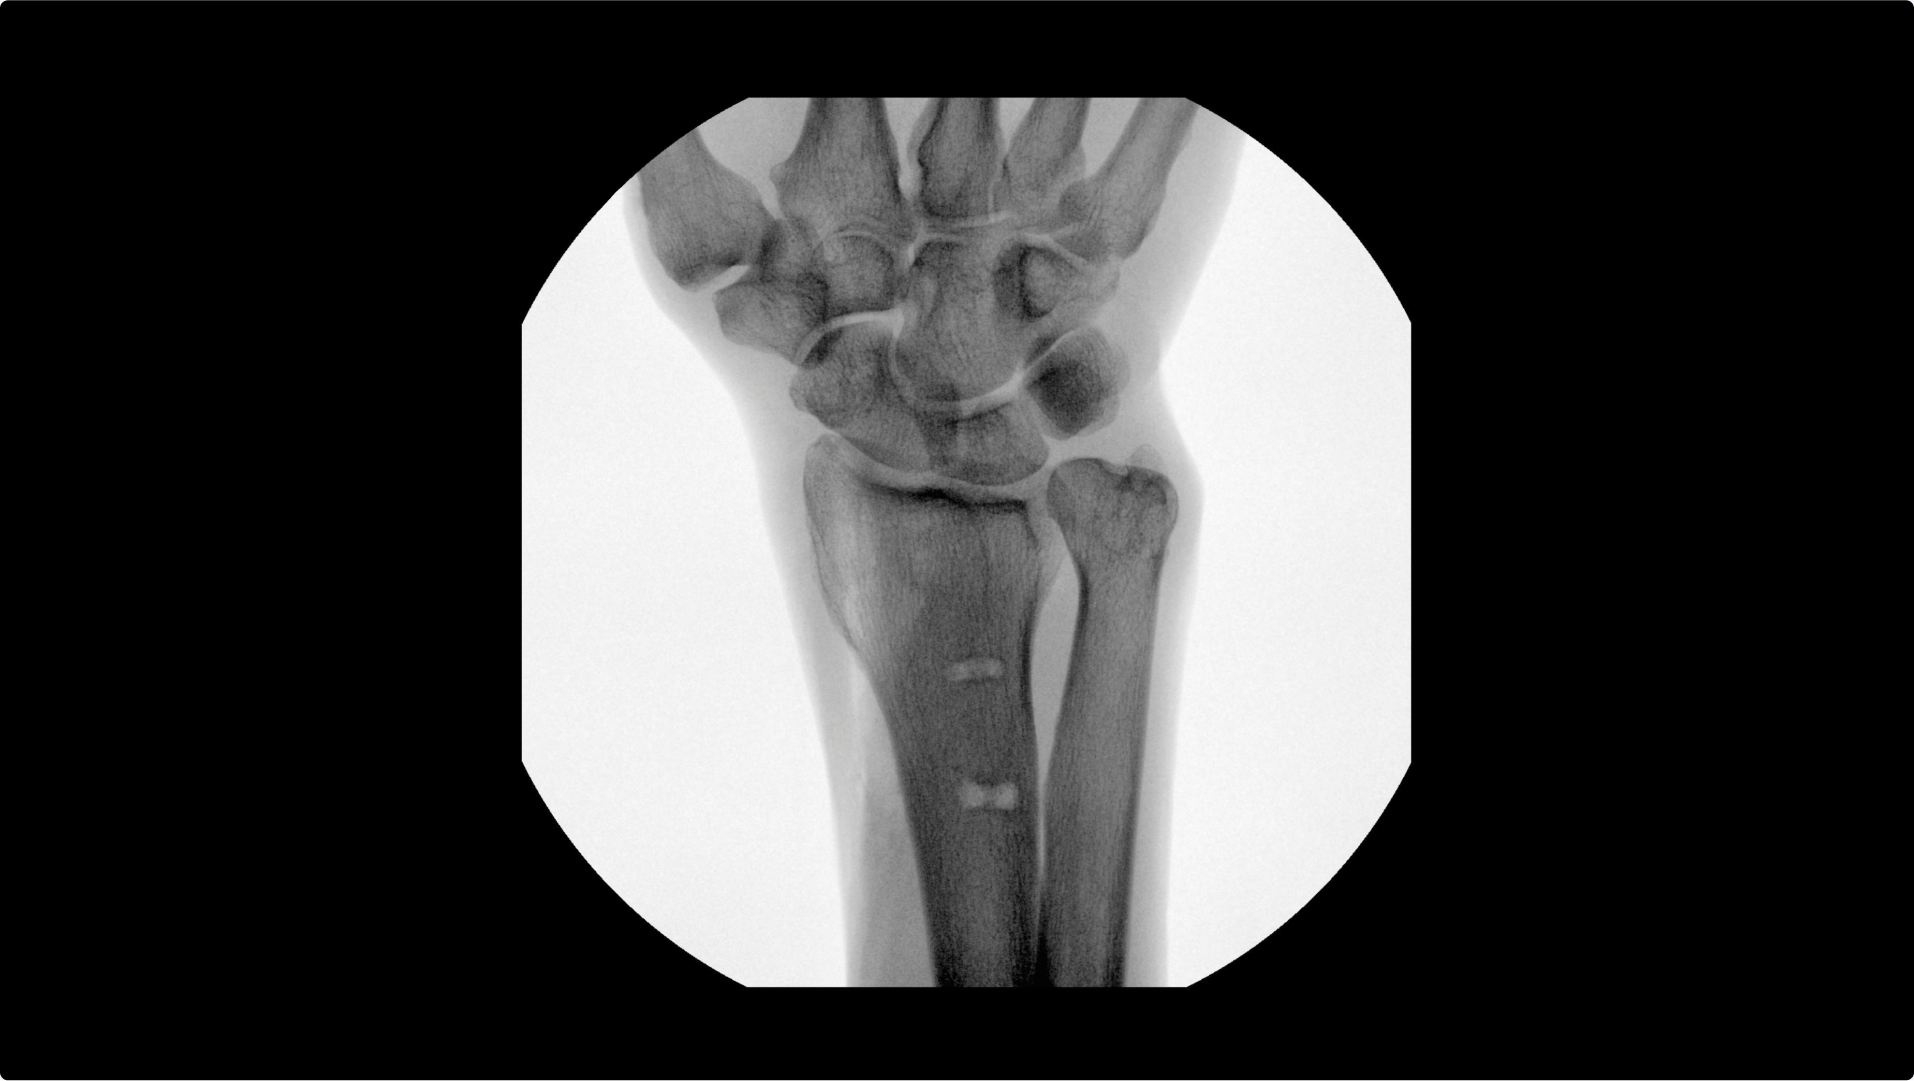

Visualizing small details such as bone fragments as well as assessing anatomical joint alignment is critical to increase clinical confidence during extremity imaging. With an OEC C-arm see clear, large images that enable you to accelerate clinical decisions and streamline your workflow during surgical procedures.

Increase clinical confidence by visualizing small details; such as bone fragments as well as assessing anatomical joint alignment with modern imaging tools such as Live Zoom, Digital Pen, and Fluorostore

Complex extremity procedures require powerful imaging systems. OEC premium C-arms perform imaging in a variety of procedures such as:

• Fracture reduction

• Scaphoid fixation

• Ulna fixation

• Distal radius fracture

• Metacarpal fixation